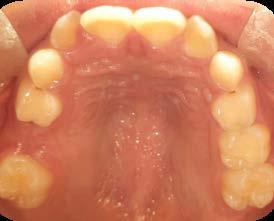

Entre los elementos que conforman al sistema estomatognático, están los dientes caninos, órganos dentales esenciales en la fisiología masticatoria; punto de unión y continuidad estética entre la línea de la sonrisa y el corredor posterior del arco dental, además de que ejercen la función de pilares estabilizadores en la oclusión fisiológica (Figura 1).

Los caninos son indispensables durante los movimientos de lateralidad y vitales para la continuidad de los arcos dentales, tanto en la dentición decidua como en la permanente; son responsables del funcionamiento y la armonía oclusal. Su posición adecuada en el arco asegura un buen contorno de la cara, sonrisa agradable y armónica con la estética facial. (Figura 2).

El canino divide su cara vestibular en 2 vertientes, una mesial que se continúa con los incisivos y otra distal que se alinea con los dientes posteriores, razón por la cual su ausencia genera alteraciones muy importantes en la oclusión y la estabilidad fisiológica del sistema estomatognático (Figura 3).

La bibliografía señala que el canino superior es el diente que presenta una mayor frecuencia de inclusión después de los terceros molares superiores e inferiores; ubicándose los caninos superiores, como los de mayor frecuencia de retención unilateral en la cara palatina y rara vez en forma bilateral (Lezcano, 2009).1

La incidencia de inclusión en los caninos superiores e inferiores tiene diferentes etiologías y similitudes. En ambos casos, el motivo principal se deriva de razones propias por su anatomía, tamaño en volumen coronal y largo de la raíz; sumado a esto, su ubicación lejana intraósea respecto al arco dental, desde la germinación y/o inicio de formación y desarrollo y, hasta alcanzar la erupción (Figura 4).

Es por lo anterior, que durante el intercambio dentario, la vigilancia periódica, a través de radiografías, análisis de modelos de estudio y una evaluación clínica, son acciones necesarias para la planeación adecuada de un tratamiento interceptivo, en caso de llegar a ser necesario, para generar los cambios y movimientos a nivel ortopédico y ortodóntico respectivamente y así evitar en lo posible una inclusión canina (Figura 7).